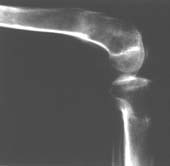

Пациент В. 53 лет, травма в феврале 2009. ДЗ. Открытый оскольчатый перелом нижней трети голени. При боли поступлении выполено ПХО, аппарат Илизарова. В последующем проводили ВХО, резекция костных отломков, укорочение 6 см, рана зажила. Была выполнена остеотомия большеберцовой кости в проксимальном отделе, резекция. Производилось тракция. На последних рентгенограммах выявлено, что одновременно с "выращиванием" регенерата произошло низведение надколенника на длину выращенного регенерата. Клинически: активное разгибание сохранено, объем движений в колене 180-110 градусов. Черными стрелками обозначен верхний край надколенника с одной и с другой стороны. Красная стрелка обозначает пальпируемую связку надколенника. Причина - остеотомия выше места прикрепления связки надколенника. Вопрос: была ли у кого подобная ситуация? Что делать? При первом обдумывании приходит решение: отсечение места прикрепления связки надколенника с костным блоком, перемещение на "правильное" место, укорочение сухожилия четырехглавой мышцы.

К сожалению, подобное осложнение "нет-нет да и возникает" при удлинении, коррекции деформации голени. В англоязычной литературе оно описано как "patella baja". Один из вариантов лечения - проксимальное перемещение надколенника приемами чрескостного остеосинтеза.

По-моему, надколенник низвелся на величину, гораздо меньшую удлинению.

Я бы уменьшил диастаз между фрагментами сантиметра на два. Судя по снимкам, регенерат это может позволить.